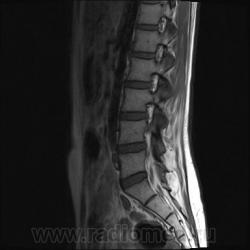

Пациентка 25 лет обратилась к неврологу с жалобами на слабость, изменение походки. Раньше не обследовалась.

Я специально сделал изображения потемнее, чтобы выделить патологию (жировую дегенерацию) именно мышечной ткани.

Гм, как это я пропустил эту публикацию. Поясничные мышцы замещены жировой тканью; т.е. Они выглядят "белыми" на Т1 и Т2, в последовательности с подавлением жира, соответственно сигнал уходит; и они "тёмные". Такую картину я видел у пожилых, иногда у пациентов после операции на позвоночнике. По поводу болезни Штейнерта, должна быть клиника, изменения и гипотония/атония мышц других локализаций. На основании только МРТ ПОП не совсем убедительно. Вот небольшая ознакомительная статейка.